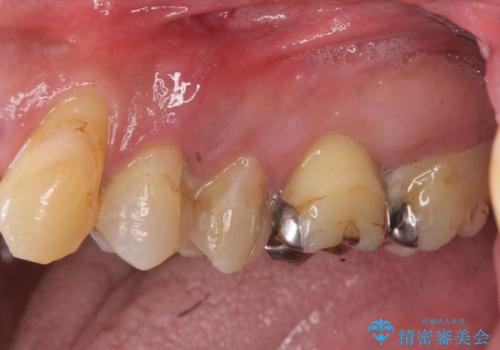

- 「全体的に歯が揺れ、今後の歯の健康に不安がある。歯周病の治療を受けたい。」、と来院されました。

精密検査の結果、重度の歯周病が認められ大きな骨の吸収を認めました。

予後の悪く保存の難しい歯を抜去し、骨の造成を含んだインプラント治療を計画します。